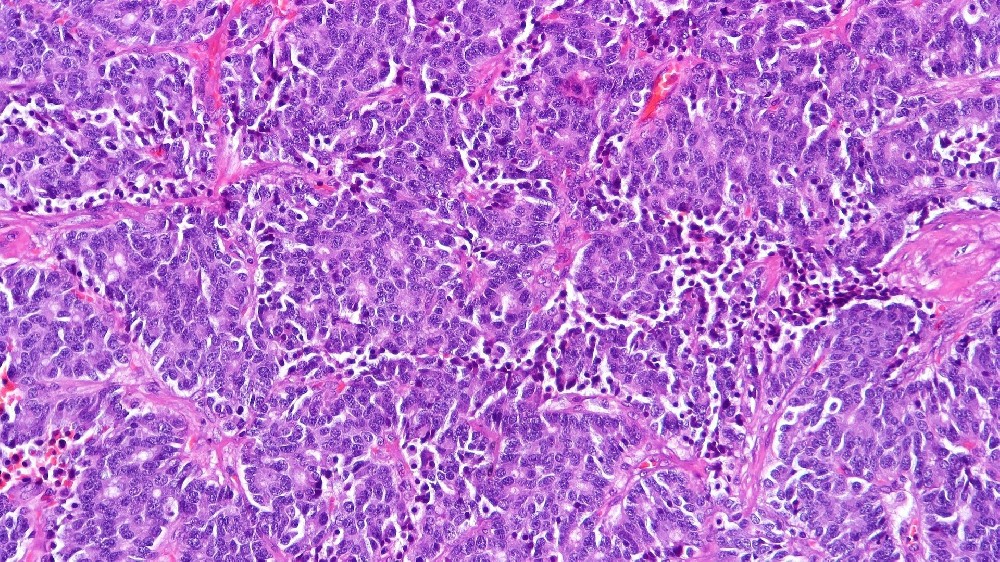

神經內分泌細胞專門合成血清素、胰島素、胰高血糖素和胃泌素等神經激素。類癌(神經內分泌腫瘤)的發展與這些細胞類型的障礙有密不可分的關係,其特點是不受控制的細胞增生和荷爾蒙過度分泌。

癌細胞的新陳代謝模式是最基本的特徵,尤其是沃伯格效應 (Warburg Effect),這是諾貝爾獎得主奧托‧沃伯格 (Otto Warburg) 首次描述的現象。癌細胞(包括類癌細胞)的新陳代謝傾向於糖酵解,消耗葡萄糖的速度比正常細胞高約 200 倍,即使在富氧的條件下也是如此。這種新陳代謝的弱點提供了獨特的針對性治療方法,突顯了創新的新陳代謝腫瘤學策略,例如李國華博士和劉國龍教授等知名專家所開創的策略。

長期的臨床評估顯示,癌症的新陳代謝適應力是治療效果有限的重要原因。神經內分泌腫瘤中的癌細胞持續展現新陳代謝的適應性,不僅呈現侵略性的沃伯格效應 (Warburg effect),消耗葡萄糖的速度幾乎是正常細胞的 200 倍,而且還利用其他新陳代謝途徑,例如谷氨酰胺新陳代謝、脂肪酸氧化和自噬途徑,有效地繞過了傳統的治療目標。

代謝抵抗機制

傳統治療類癌(神經內分泌腫瘤)的一個關鍵障礙涉及代謝抵抗機制。最近的 Nature Medicine 研究 (2024) 強調了癌症神經內分泌細胞間 DNA 修復活性增強的重要作用,顯示與正常細胞相比,DNA 修復酵素的表達量增加了高達 400%。這種新陳代謝適應性大大有助於抵抗 DNA 損傷療法,如化療和放射治療。

DNA 修復能力增強 (~400% 高於正常細胞)

葡萄糖消耗率增加約 200 倍的沃伯格效應

谷氨酰胺依賴性和代謝可塑性會增加抵抗力

針對標準細胞凋亡通路的療法成效有限

因此,由於神經內分泌腫瘤所展現的這些複雜生存機制,傳統治療方法的療效仍會大打折扣。